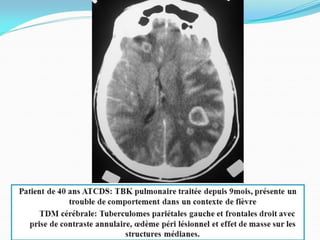

CAS CLINIQUE

• Occlusion des sinus veineux cérébraux souvent associés à une

thrombose des veines corticales

• SCANNER et ANGIO SCANNER: Sans /Avec inj:

Sans inj: hyperdensité spontanée du thrombus au sein d’un sinus

veineux=SIGNE DU TRIANGLE DENSE.

• SCANNER avec inj: Zone hypodense d’un sinus(thrombus) cernée

d’une importante prise de contraste de la paroi du sinus réalisant

le SIGNE DU DELTA ou du TRIANGLE VIDE: ++++SIGNE DIRECT